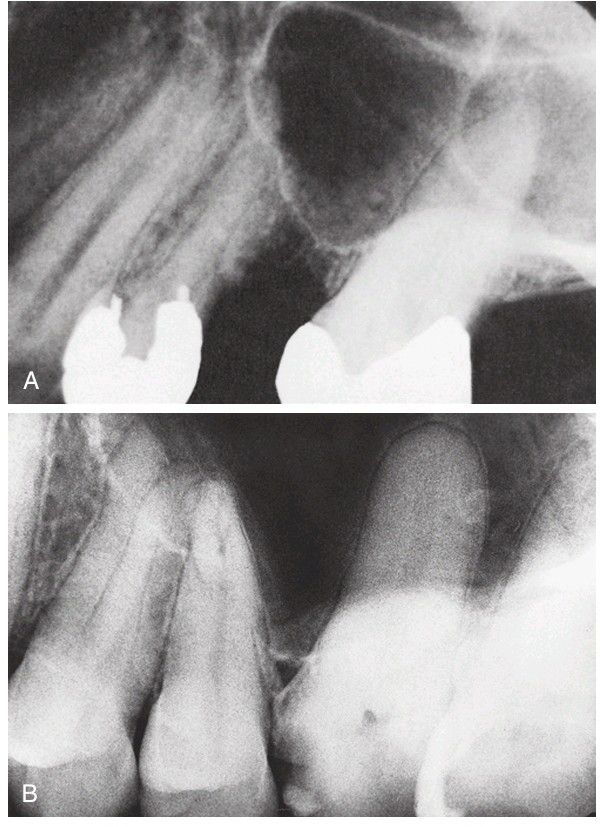

Maxillary sinus perforation

(A) Floor of sinus associated with roots of teeth. If extraction is required, the tooth should be removed surgically. (B) Maxillary molar teeth immediately adjacent to the sinus present increased danger of sinus exposure.